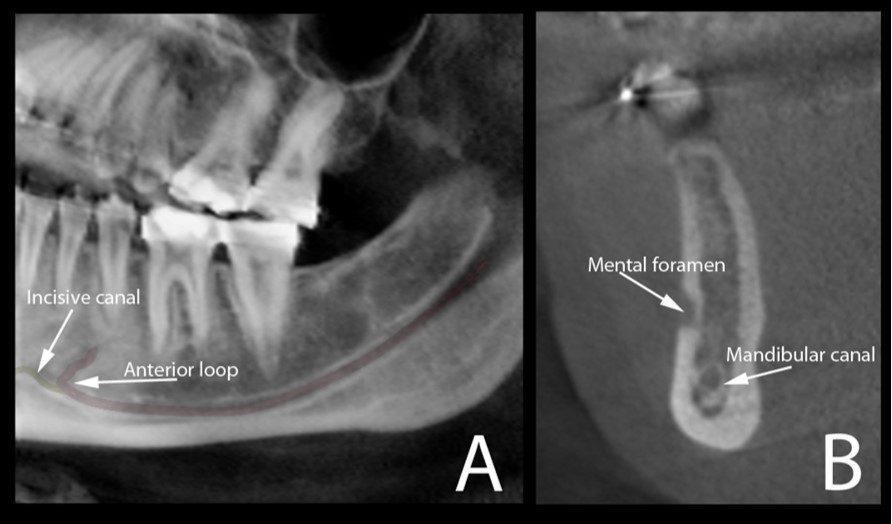

The typical images from modern human and great apes with different anatomical features were shown in Figure 1 and Figure 2. A group of variables were categorized as: the presence of the incisive canal, the number of mandibular canal bifurcations, the potential occurrence of an anterior loop, the presence of the incisive canals, its end-point and connection of the incisive to the lingual canals (Figure 3). Interspecific variability was determined by comparing contemporary human and great ape mandibles. In this analysis, mandibles from the different geographical locations were grouped in the human group, and then compared to mandibles of chimpanzees and gorillas.

Figure 3.Cone beam CT image (A) shows the oblique reconstruction of the volume of interest at the region of premolars. In this reconstruction, the anterior loop of the mandibular canal can be clearly observed before the start of the incisive canal. The appearance of this anterior loop in a cross-sectional view is shown in image (B).